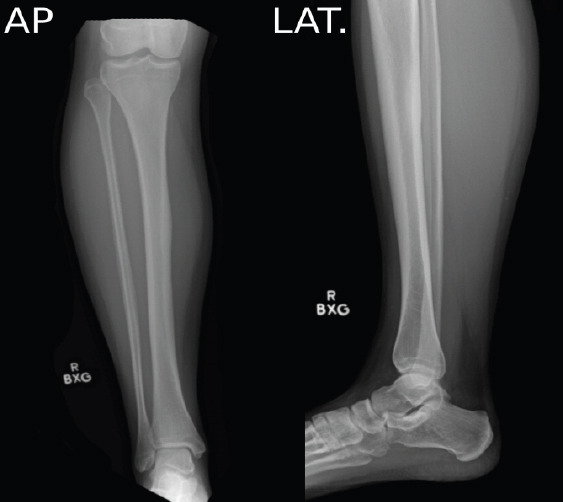

Case report: A 31-year-old female presented to our clinic with chronic neuropathic pain after sustaining a blunt injury to the medial aspect of the right leg 15 years previously while playing softball. Her pain was localized to the anteromedial lower leg and was not relieved by medical management and therapy. She temporarily had complete relief of her symptoms with ultrasound-guided hydrodissection. She was treated with surgical exploration and neurolysis, and postoperatively, the patient had no complications and complete relief of her pain.

Conclusion: We present a case of a 31-year-old patient who had perineural scarring and chronic neuropathic pain necessitating surgical exploration and neurolysis. Our case highlights the importance of investigating the etiology of neuropathic pain with several modalities and demonstrates the utility of ultrasound-guided peripheral nerve hydrodissection for both therapeutic and diagnostic purposes.